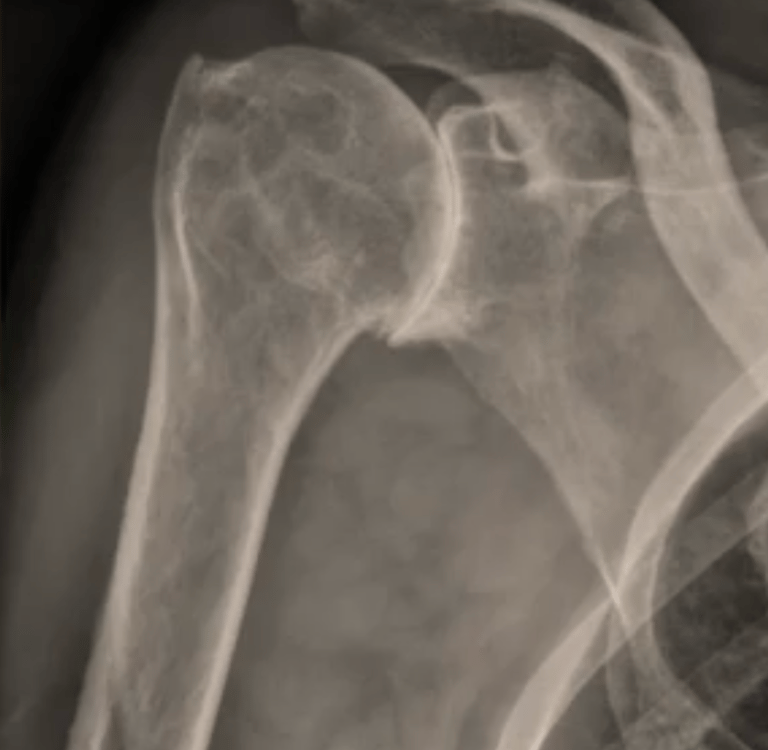

Vous présentez une arthrose de l'épaule / gléno-humérale ; ET une coiffe des rotateurs détériorée (1)

La conséquence est une omarthrose / usure excentrée de l'épaule ( 2).

Dans les forme évoluées, ou en cas d'échec du traitement médical, une prothèse totale d'épaule inversée est proposée.